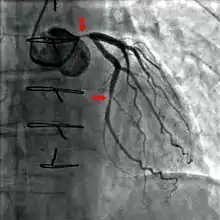

Diagnostic procedures

During coronary catheterization (often referred to as a cath by physicians), blood pressures are recorded and fluoroscopy (X-ray motion picture) shadow-grams of the blood inside the coronary arteries are recorded. In order to create the X-ray pictures, a physician guides a small tube-like device called a catheter, typically ~2.0 mm (6-French) in diameter, through the large arteries of the body until the tip is just within the opening of one of the coronary arteries. By design, the catheter is smaller than the lumen of the artery it is placed in; internal (intra-arterial) blood pressures are monitored through the catheter to verify that the catheter does not block blood flow (as indicated by "dampening" of the blood pressure).

The catheter is itself designed to be radiodense for visibility and it allows a clear, watery, blood compatible radiocontrast agent, commonly called an X-ray dye, to be selectively injected and mixed with the blood flowing within the artery. Typically 3–8 cc of the radiocontrast agent is injected for each image to make the blood flow visible for about 3–5 seconds as the radiocontrast agent is rapidly washed away into the coronary capillaries and then coronary veins. Without the X-ray dye injection, the blood and surrounding heart tissues appear, on X-ray, as only a mildly-shape-changing, otherwise uniform water density mass; no details of the blood and internal organ structure are discernible. The radiocontrast within the blood allows visualization of the blood flow within the arteries or heart chambers, depending on where it is injected.

If atheroma, or clots, are protruding into the lumen, producing narrowing, the narrowing may be seen instead as increased haziness within the X-ray shadow images of the blood/dye column within that portion of the artery; this is as compared to adjacent, presumed healthier, less stenotic areas.